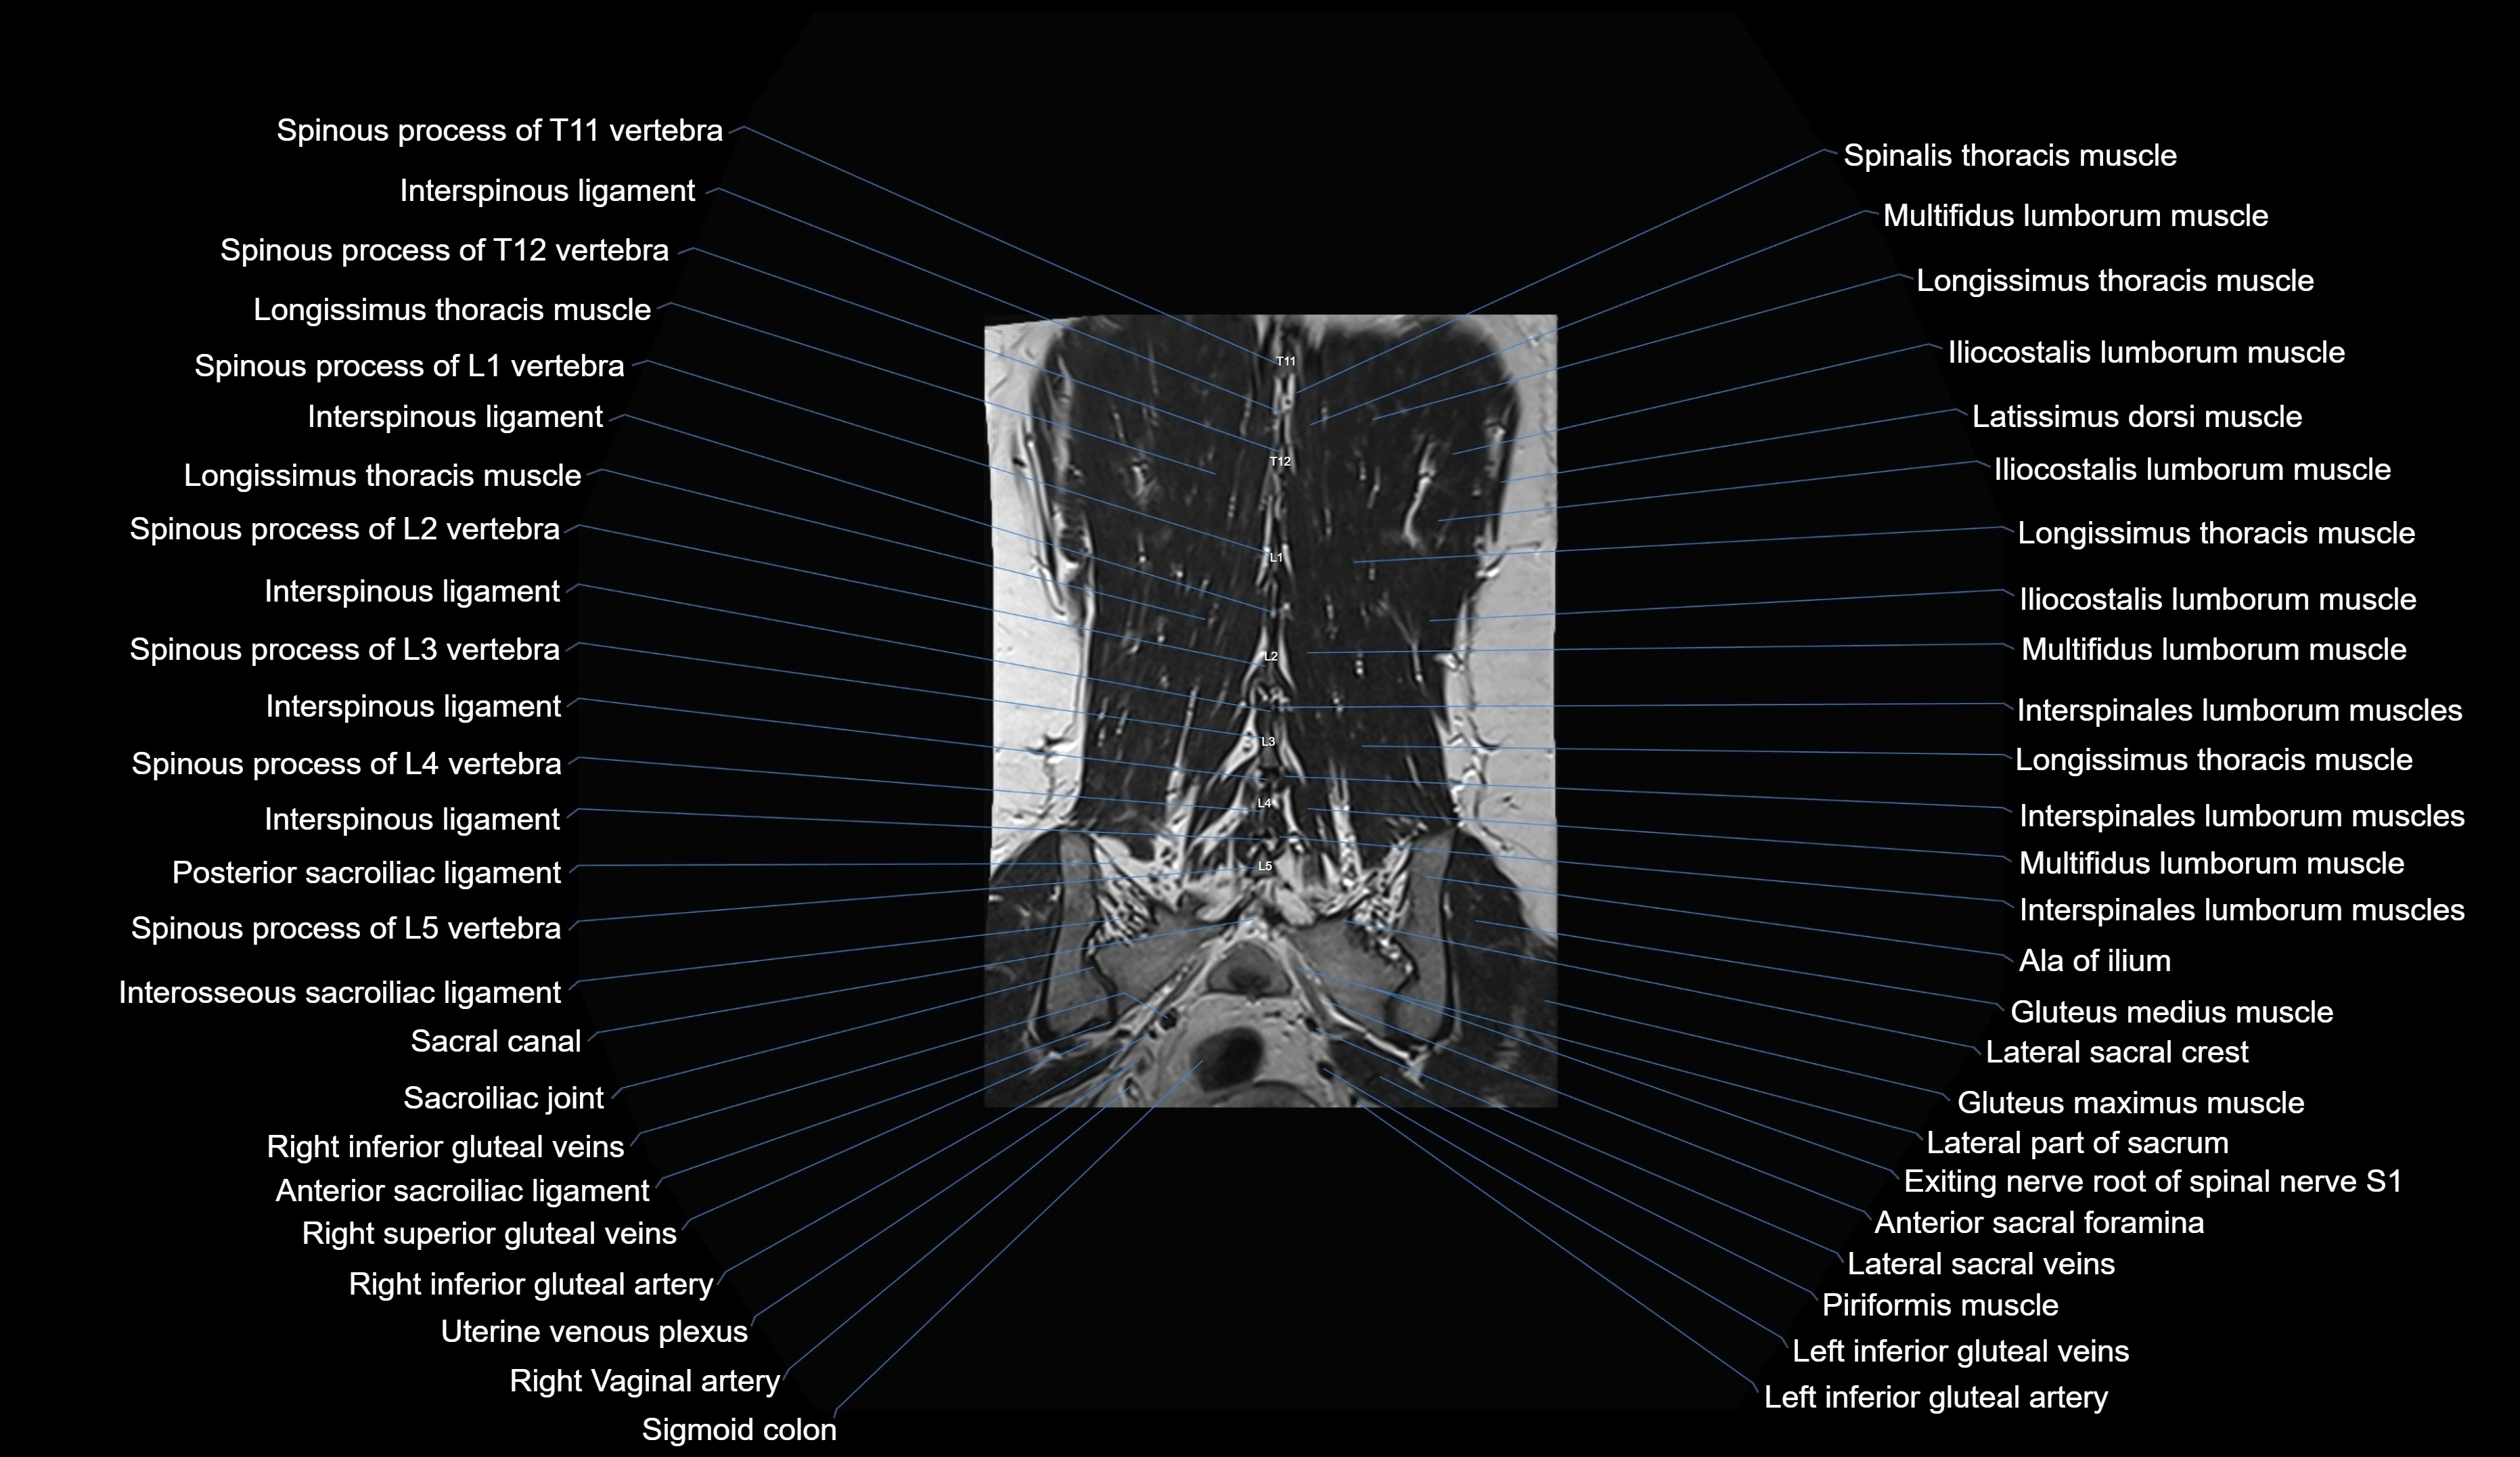

MRI images